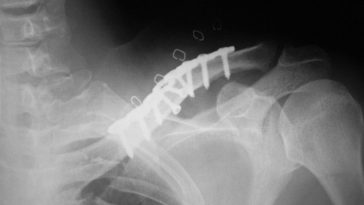

Exploring the Link between Clavicle Fixation Vein Thrombosis and Thoracic Outlet Syndrome

Introduction: Outdated Technology and the Modern Healthcare Landscape In today’s digital era, when every piece of healthcare information can easily be accessed with just a few clicks, it is surprising to encounter messages warning us that our browser is outdated. This situation is a clear reminder that even though we live in a time of […] More